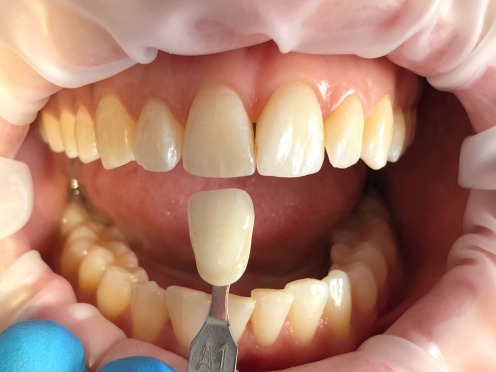

Il nostro studio offre una vasta gamma di materiali di vari colori, luminosità e gradi di saturazione al fine di raggiungere risultati estetici e totalmente naturali.